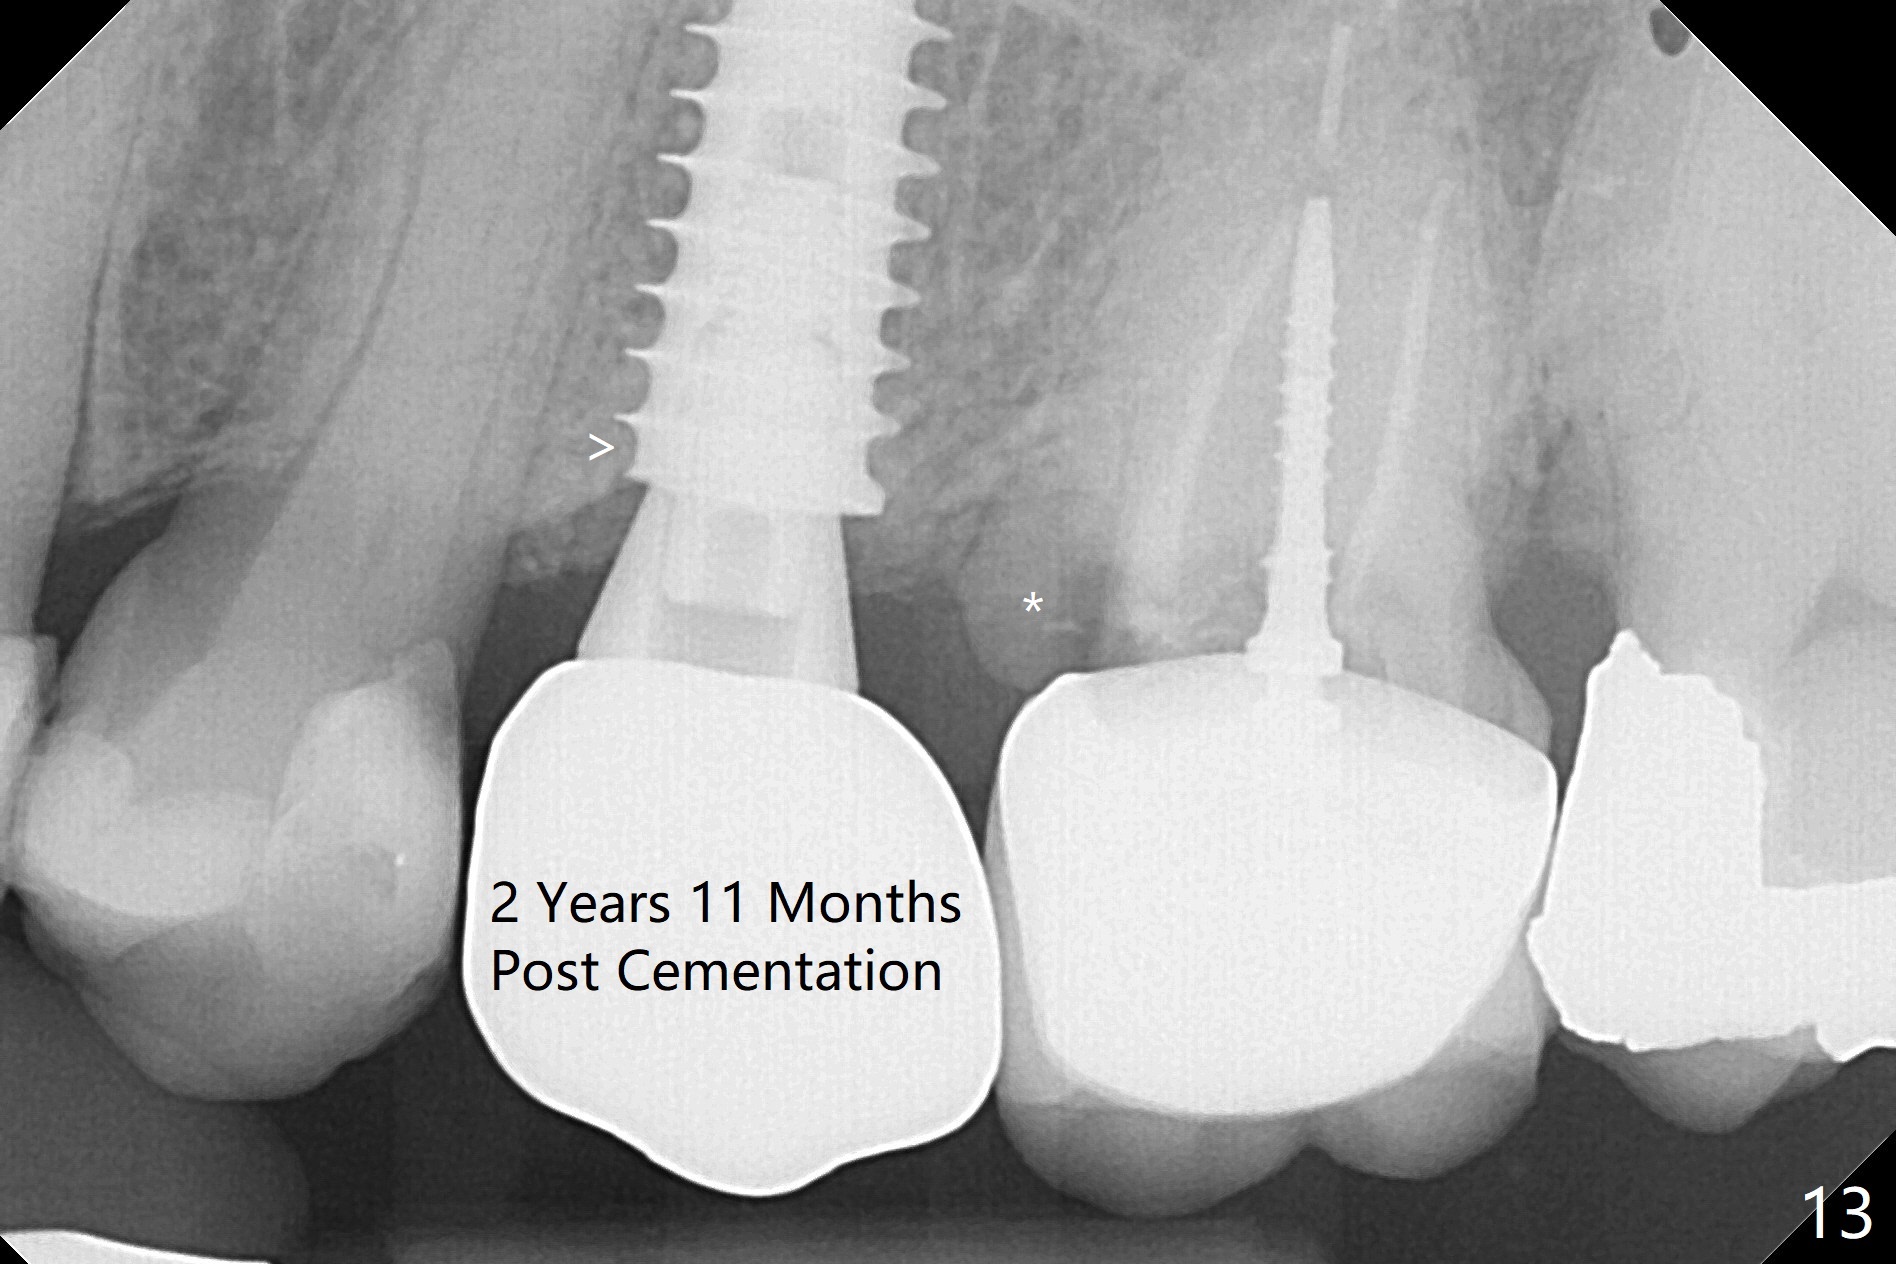

Since the apical native bone is limited at #13 after extraction, no PA is taken until a 4x11 mm dummy implant is placed after 1.6 mm and 3.3 mm drills for 13 mm (Fig.1). After using Lindamann bur to move the osteotomy distal and reusing 3.3 mm drill, the trajectory of a 4.5x11 mm IBS dummy implant improves (Fig.2,3 with low stability). When the implant is removed, the buccal portion of the socket is found to be perforated (Fig.4 P). Although the reason for the perforation is unknown, it is repaired by insertion of a piece of PRF plug, followed by allograft. #1 and 2 in Fig.4 represent the 1st and 2nd osteotomies, as shown in Fig.1 and 2, respectively. The trajectory of the final 5x13 mm implant is acceptable (Fig.5-7, different angulations), so is insertion torque (45 Ncm). After placing a 5.5x4(4) mm abutment, an immediate provisional is fabricated (Fig.8 P) with occlusal clearance (*). The interdental papillae remain in place 12 days postop (Fig.9 *). There is no sign of postop sinus infection. The provisional is loose 18 days postop; the abutment is changed to 5x4(3) mm (Fig.10). It is difficult to catch the mesial margin of the abutment for impression 4 months postop, due to poor oral hygiene and the short cuff (3 mm, Fig.11). The appointment for impression is rescheduled with emphasis on oral hygiene and no wearing the provisional for a few days prior to next appointment. Bone has grown into the space between the 1st and 2nd threads 5 months post cementation (Fig.12) and the bone is normal, solid and dense 2 years 11 months post cementation (Fig.13 >). There is mesial open margin of the tooth #14 (Fig.13,14 *).